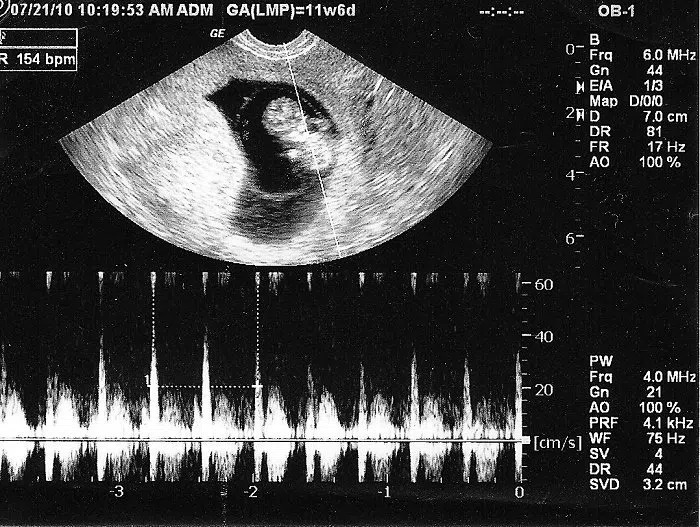

| 5 tuần | 80 – 103 |

| 6 tuần | 90 – 110 |

| 7 tuần | 110 – 130 |

| 8 tuần | 140 – 170 |

| 9 tuần | 155 – 195 |

| 10 tuần | 160 – 180 |

| 11 – 12 tuần | 150 – 170 |

| 13 – 20 tuần | 140 – 160 |

| 21 – 30 tuần | 130 – 150 |

| 31 – 40 tuần | 120 – 160 |

Theo Hiệp hội Sản phụ khoa Hoa Kỳ (ACOG), khoảng nhịp tim thai bình thường trong phần lớn thai kỳ là 110 – 160 lần/phút.